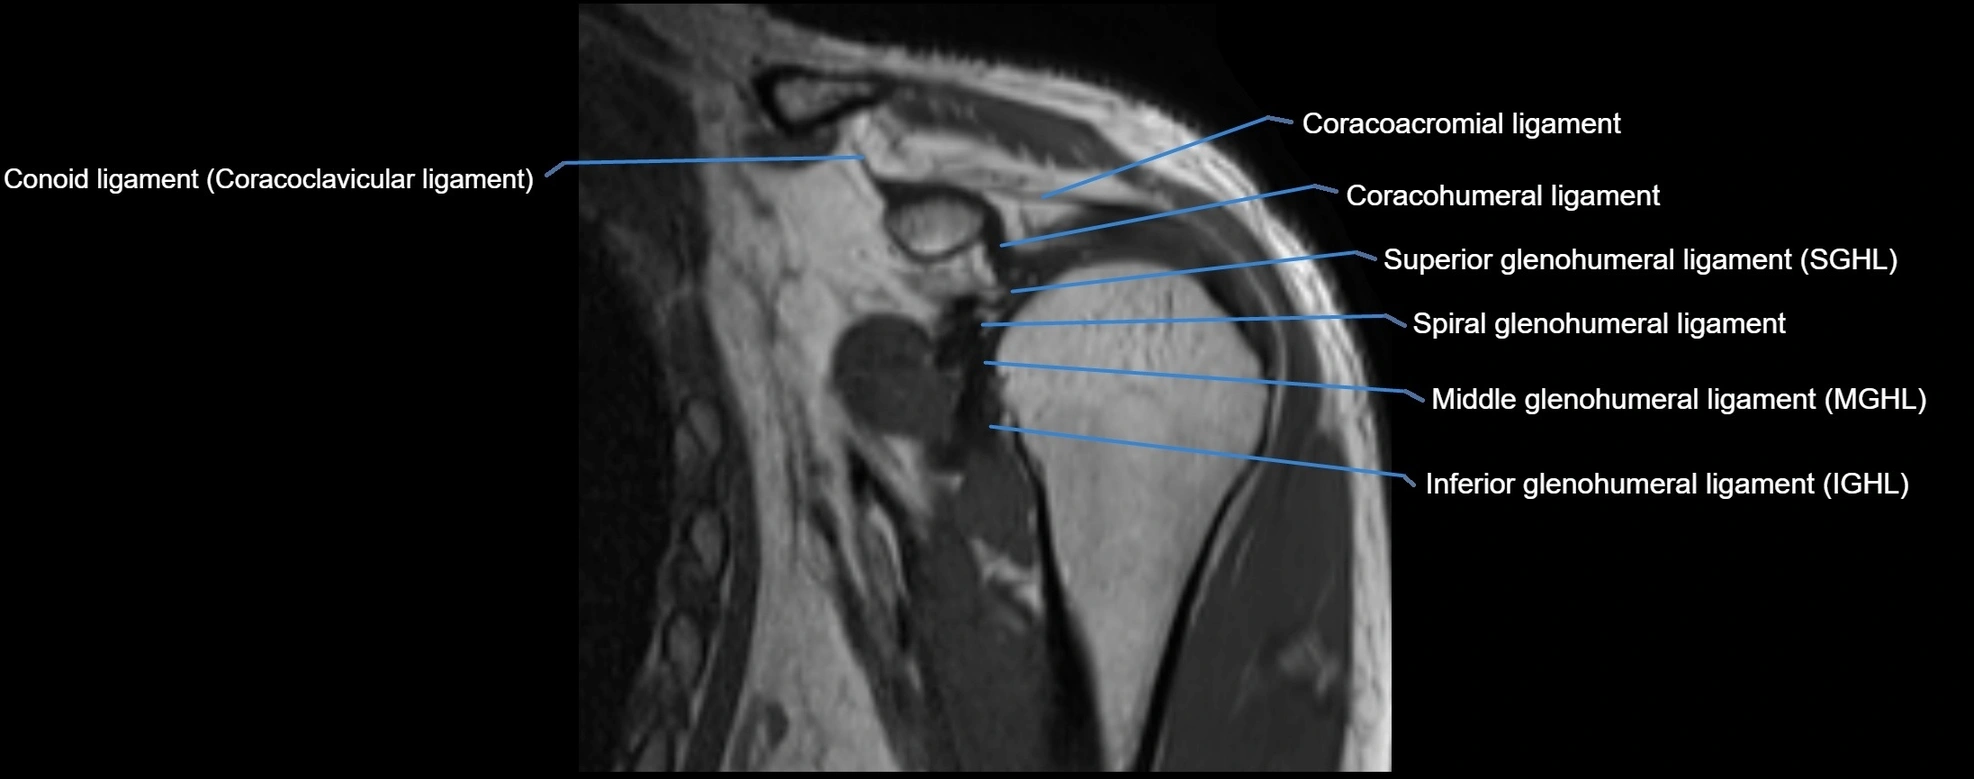

MRI images

image

MRI Appearance

• T1-weighted images:

• Normal ligament: Low signal (dark linear band) spanning acromion to clavicle.

• Surrounding fat planes: Bright, delineating the ligament clearly.

• Marrow of clavicle and acromion: Bright due to fatty content.

• Tears: Discontinuity or irregular thickening with intermediate-to-bright signal.

• Chronic injury: Thinning, fraying, or irregular low-signal fibers with adjacent scarring.

• T2-weighted images:

• Normal ligament: Low signal, homogeneous.

• Partial tear or sprain: Focal hyperintensity or thickening.

• Complete tear: Discontinuity with fluid-bright gap between clavicle and acromion.

• Associated edema: Bright signal in distal clavicle or acromion marrow.

• STIR:

• Normal ligament: Dark linear band.

• Injury or inflammation: Bright hyperintense signal in and around ligament fibers.

• Highlights periligamentous soft-tissue edema, especially in acute trauma.

• Proton Density Fat-Saturated (PD FS):

• Normal ligament: Low signal, uniform thickness.

• Partial tear or sprain: Bright signal or contour irregularity.

• Complete tear: Clear discontinuity with bright signal gap and joint effusion.

• Excellent for assessing joint capsule, coracoclavicular ligaments, and periarticular edema.